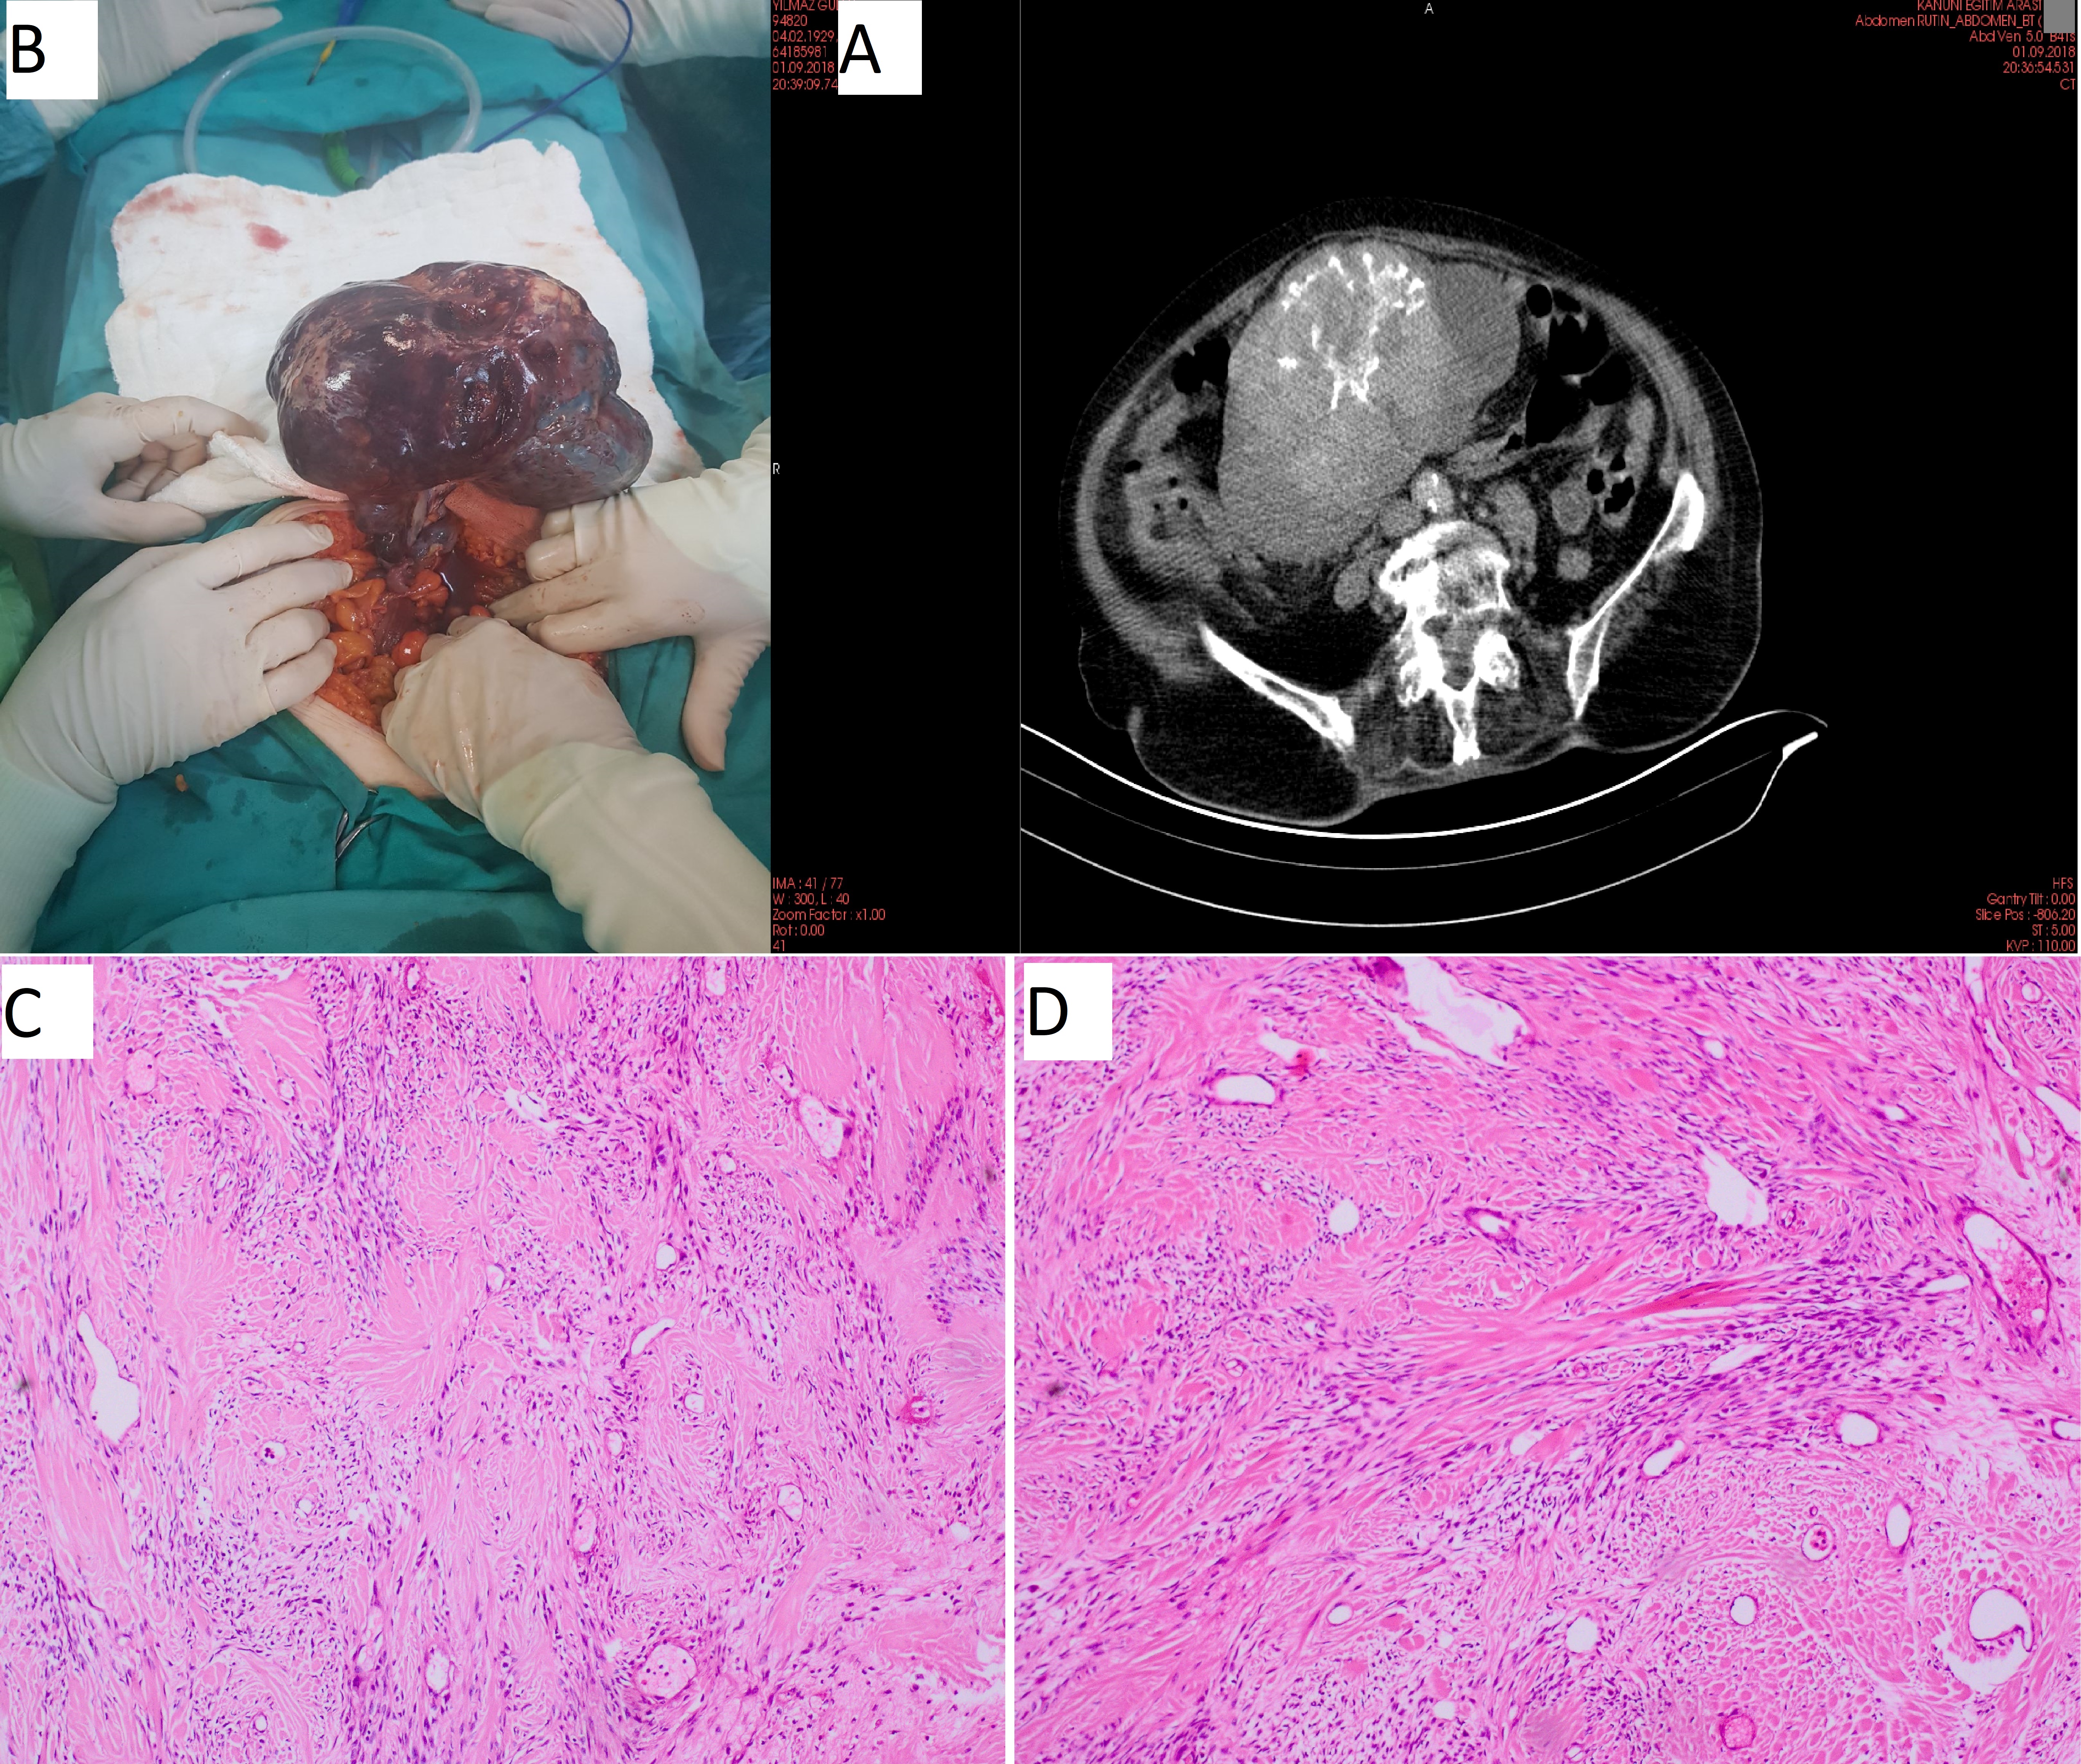

Open AccessCase Report

27 Weeks Abdominal Pregnancy wıth Mısdıagnosed at the Fırst Center, A Case Report

Recep ERİN, Kadri TEZEL, Ahmed ISAK, Samira AHMED, Mustafa KUŞAK

International Journal of Innovative Research in Medical Science·September 26, 2019

How to Approach to Torsional Adnexal Mass in a Geriatric Age Woman: A Case Report and Literature Review

Recep ERİN, Yeşim BAYOĞLU TEKİN, Fatma Gülgün KOÇAK